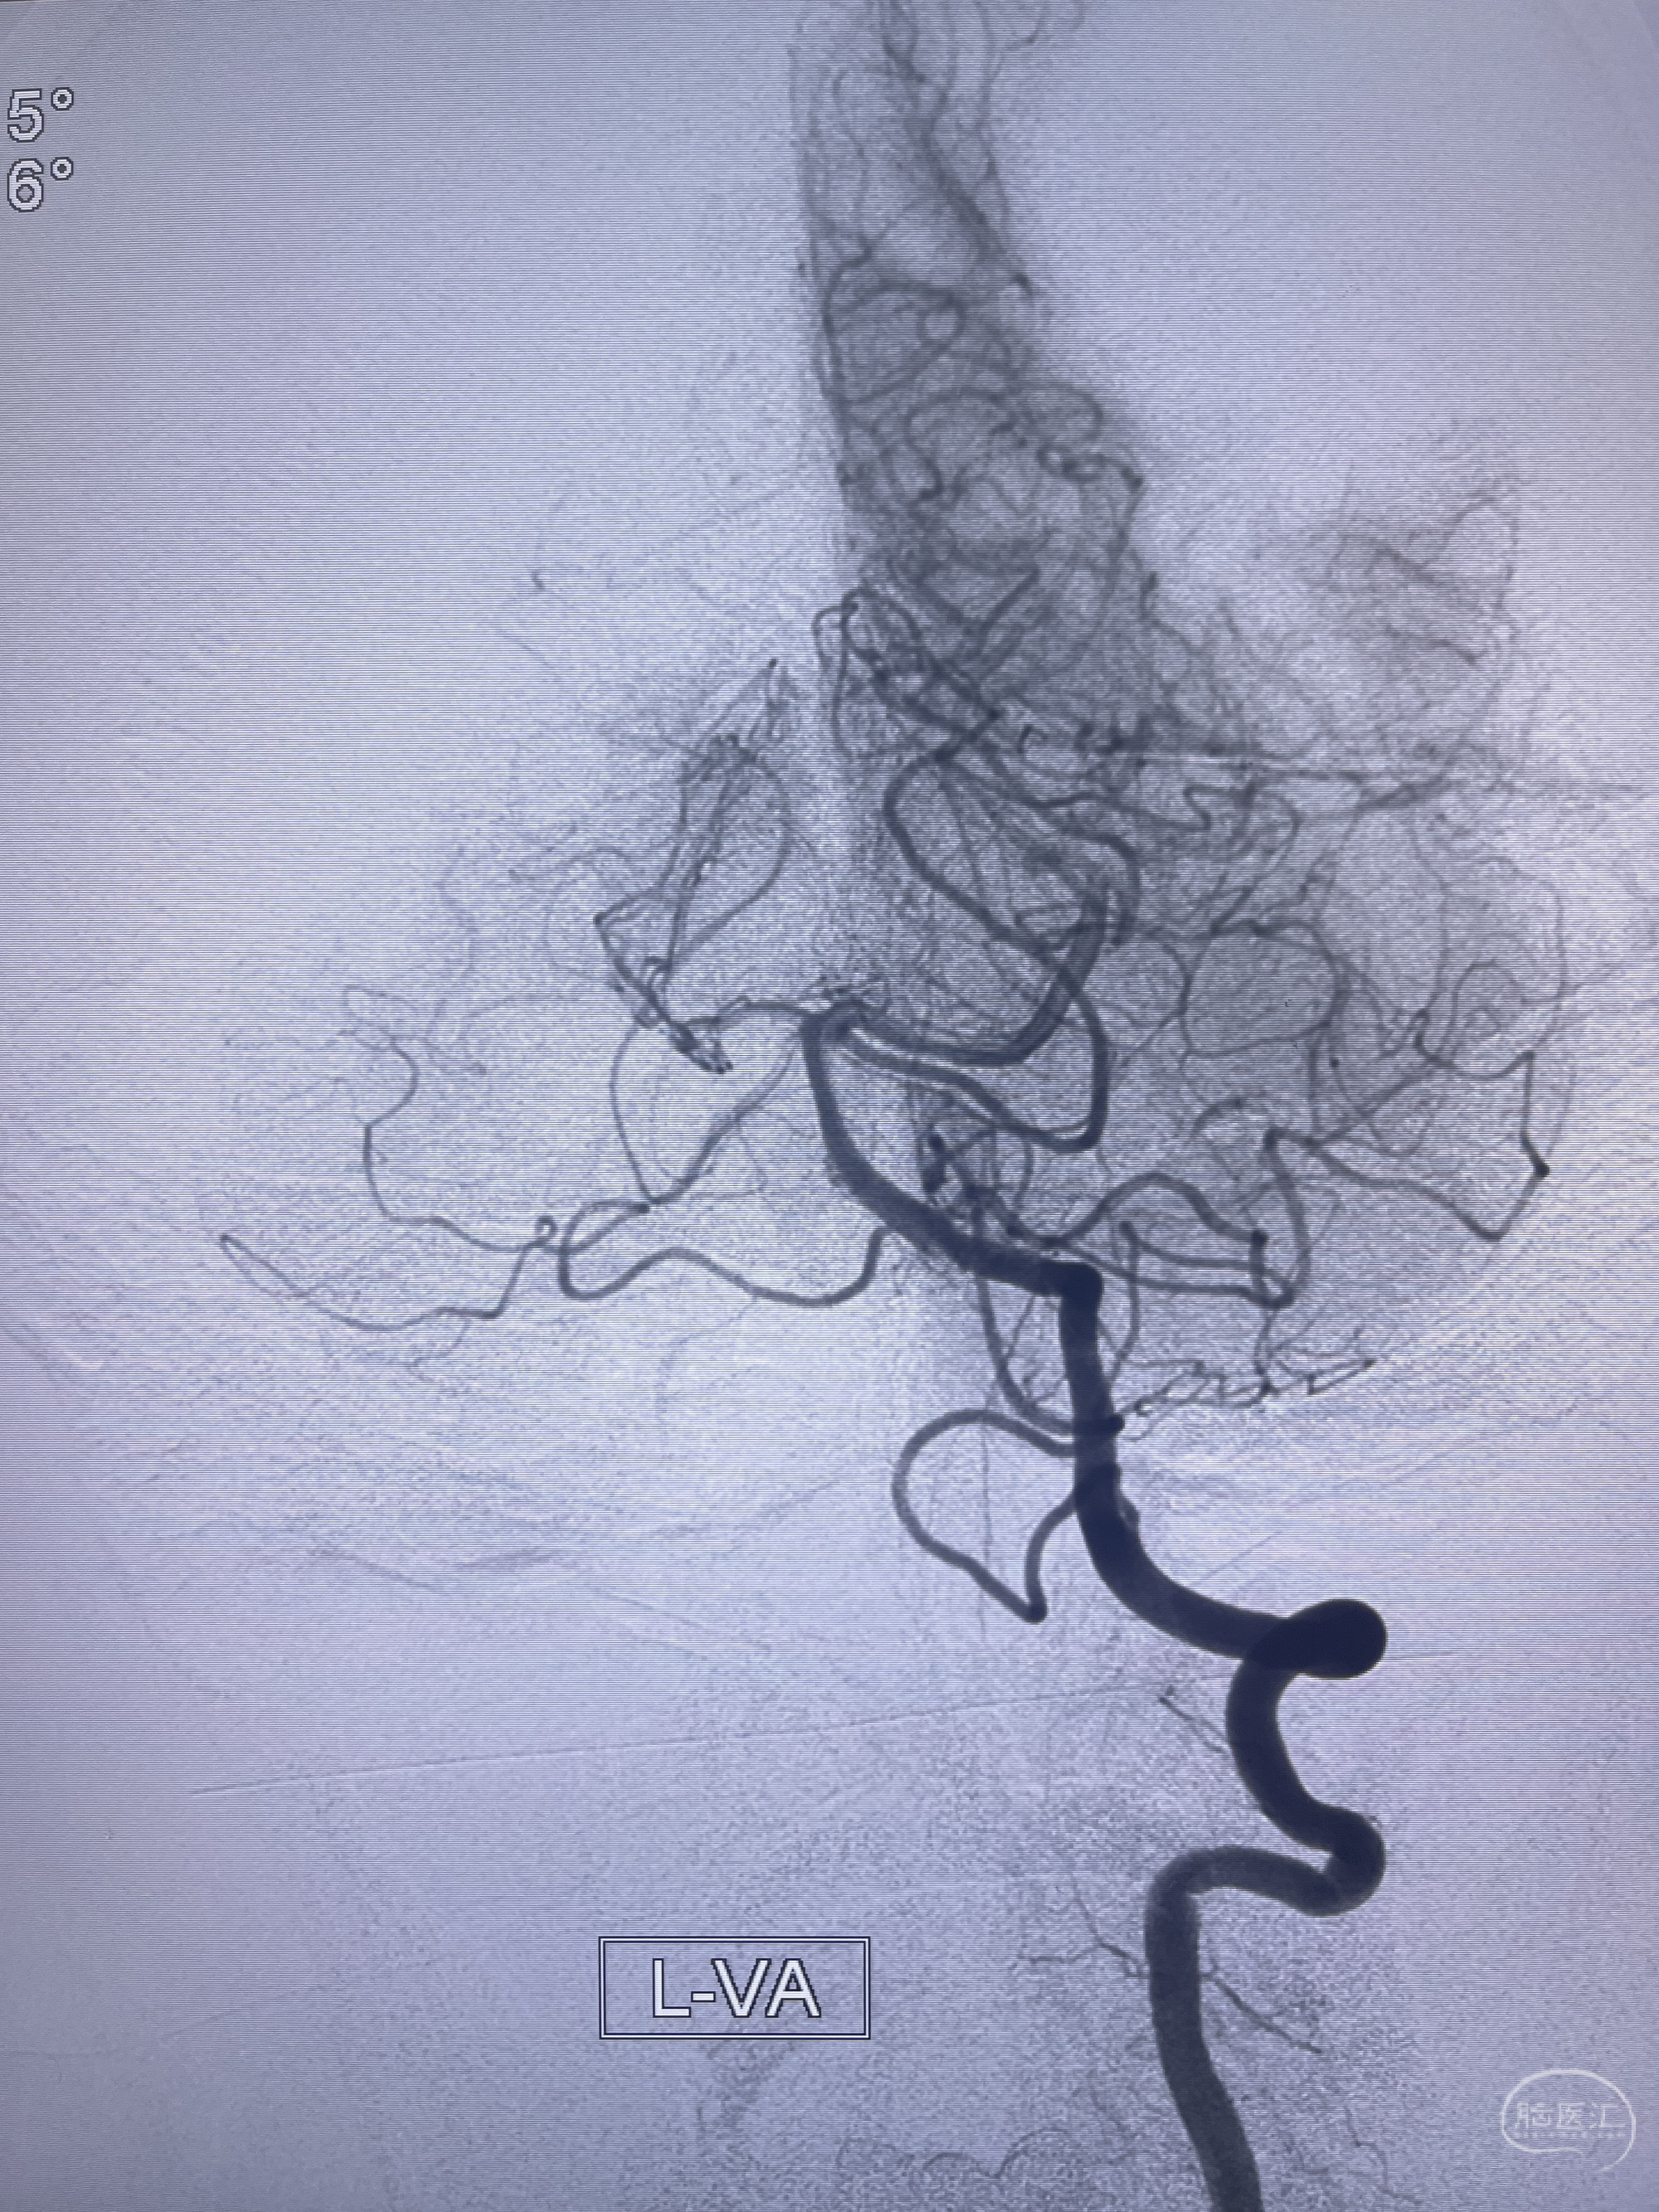

202.04.28脑血管造影:右侧大脑后动脉远段闭塞,右侧椎动脉V4段可见“囊状造影剂填充影”,大小7.64*7.65mm,可见PICA由动脉瘤发出;

1.普通支架辅助弹簧圈栓塞?

2.密网支架辅助弹簧圈栓塞?